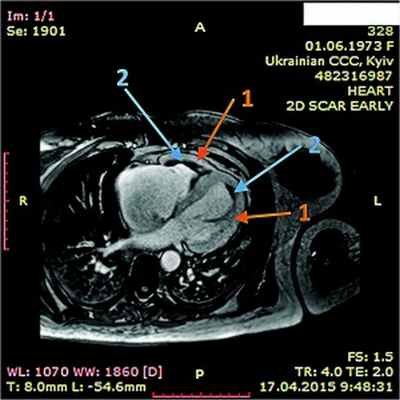

При рентгенологическом обследовании органов грудной клетки обнаруживают кардиомегалию и признаки венозного застоя в легких. Изменения ЭКГ не специфичны. Частые находки – нарушения ритма сердца, особенно фибрилляция предсердий (ФП). В диагностике заболевания основную роль играет эхокардиография (ЭхоКГ), позволяющая обнаружить локальное (реже – диффузное) утолщение верхушки одного или обоих желудочков с вовлечением в патологический процесс хорд, умеренную митральную или трикуспидальную регургитацию, пристеночные, особенно верхушечный, крупные тромбы. Показательным является «рестриктивный тип» ремоделирования сердца и внутрисердечной гемодинамики – очевидное преобладание объема предсердий над объемами желудочков. Систолическая функция, как правило, сохранена, но диагностируется диастолическая дисфункция – рестриктивный тип трансмитрального/транстрикуспидального кровотока. Наиболее информативными методами исследования на сегодняшний день являются магнитно-резонансная томография (МРТ) и мультиспектральная компьютерная томография с контрастированием 14. В литературе описан случай динамического наблюдения за развитием эндокардита Леффлера с серией одновременно производимой позитронно-эмиссионной томографии и контрастированной МРТ с выделением стадий: бессимптомной, острой некротической, симптомной тромботической и фибротической [13]. Выполнение эндомиокардиальной биопсии миокарда правого (ПЖ) или левого (ЛЖ) желудочка позволяет подтвердить или опровергнуть диагноз эндокардита Леффлера.

14.04.2015 г. пациентка была госпитализирована в Национальный научный центр «Институт кардиологии им. Н.Д. Стражеско» в отделение некоронарогенных заболеваний сердца и клинической ревматологии, где был выставлен (подтвержден и уточнен) диагноз: ГЭС. Эндокардит Леффлера с поражением ЛЖ и ПЖ. Массивные пристеночные тромботические наслоения в ПЖ. Апикальный тромб ЛЖ. Мелкие тромбы в ушках обоих предсердий. Синусовая тахикардия. Единичные желудочковые ЭС. Перикардит с небольшим количеством жидкости. СН IIА ст. со сниженной сократительной функцией ЛЖ ІІ ФК по NYHA. Аутоиммунный тиреоидит, эутиреоз. Токсокароз, висцеральная фаза.

ЭхоКГ: Патологические изменения миокарда ПЖ с утолщением стенок до 18 мм. Диффузный гипокинез стенок ЛЖ с дискинезом верхушки – ФВ 44%. В области верхушки ПЖ – наслоения между листками перикарда. Небольшое количество жидкости в полости перикарда – по ЗСЛЖ до 5 мм. Таким образом, в динамике на ЭхоКГ наблюдалось снижение сократительной функции ЛЖ на фоне его гипертрофии и, несмотря на проведенную высокодозовую терапию гормонами, не уменьшилась гипертрофия ПЖ.

В ходе серии динамических МРТ с контрастированием (рис. 7-11) выявлены массивные пристеночные тромботические наслоения в ПЖ, апикальный тромб ЛЖ.